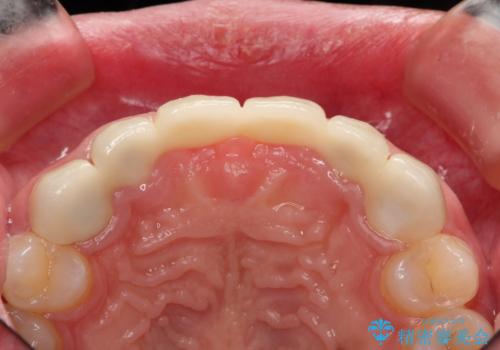

- 数ヶ月前に治療終了したブリッジの歯ぐきの違和感が強く、改善を求めて来院されました。

歯ぐきは著しく腫れ、少し触ると出血してしまうような状態であったためブリッジの再作製・歯周外科を用いた歯肉環境の改善を計画します。

セラミック治療は見た目の美しさに目を奪われがちですが、快適な使用感を達成するために歯肉環境・根管内の感染の除去が重要なポイントとなります。